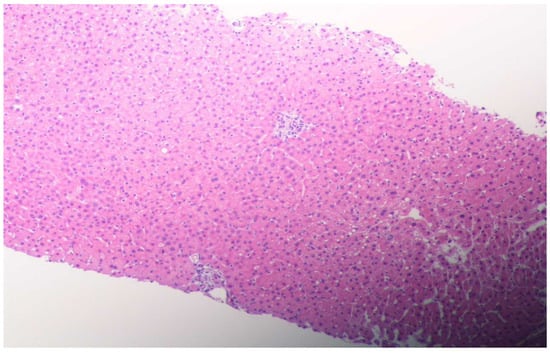

2. Case Presentation